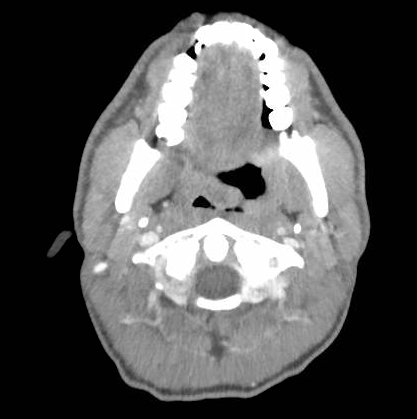

The photograph demonstrates an area of ulcerative tissue at the left palatine tonsil without surrounding erythema or purulent drainage. The computed tomography (CT) scan shows a large ulceration of the left soft palate and palatine tonsil (red arrow). There is no evidence of skull base osteomyelitis. There is suppurative lymphadenopathy with partial left jugular vein compression due to mass effect (yellow highlight). There is mild nasopharyngeal airway narrowing with architectural distortion (blue arrow), but no other evidence of airway obstruction.